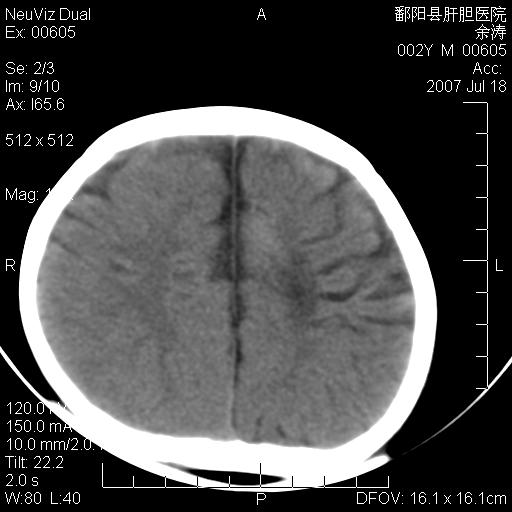

男性 2岁:平时智力障碍。外伤后行颅脑平扫。

左颞叶“萎缩”,可见不规则高密度影,并左侧室扩大,呈负占位效应...支持考虑先天发育异常(血管发育畸形)可能性大,建议结合进一步检查了解。

脑裂畸形;左侧脑脑萎缩;透明隔囊肿;血管畸形?

该病人应该还有胼胝体发育不全